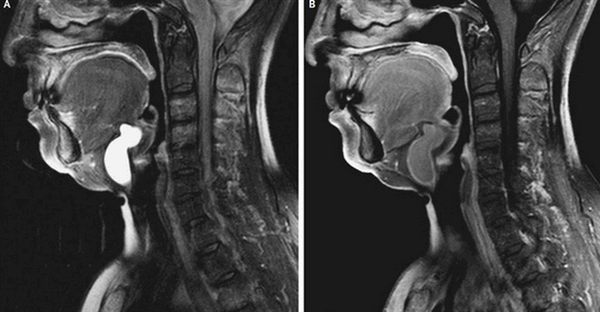

Объемное образование в области гортани (стрелки): проекция спереди и сбоку

МРТ показывает рак гортани и других органов. Томография является предпочтительным методом визуализации новообразований. Чтобы улучшить достоверность и качество снимков, врачи рекомендуют проводить исследование с контрастированием. МРТ покажет:

- размер очага;

- расположение опухоли;

- контур и внутреннюю структуру;

- особенности кровотока;

- состояние лимфатических узлов и др.

При помощи полученных данных доктор сможет установить диагноз, предположить, есть ли у новообразования злокачественный потенциал, определить наличие метастазов и стадию заболевания. Раковая опухоль чаще выглядит как бугристый элемент, прорастает соседние ткани. Биопсия (метод диагностики, дающий информацию о клеточном строении), имеет решающее значение в подтверждении онкологии. Результаты томографии помогут определить тактику лечения, объем операции, сделать прогноз при раке горла, покажут динамику состояния.